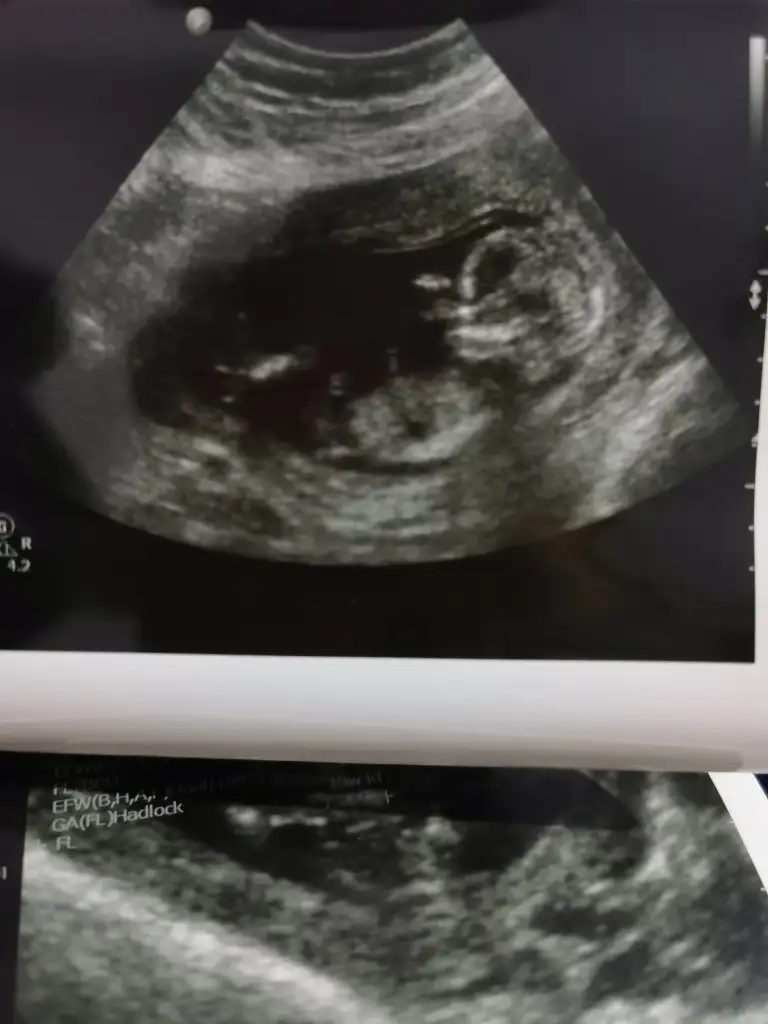

Kızlar 13+1 haftayız. Cinsiyet tahmini edebilecek var mı? Doktor söyleyemedi 🙊

Screenshot_20220202-173716_Gallery.webp